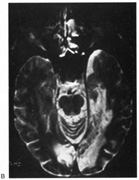

Fig. 5. Macula-splitting hemianopia. A 47-year-old man with AIDS and sudden onset of poor vision. A. Fields show complete left hemianopia. B. MRI shows lesion of right lateral occipital cortex, affecting distal optic radiations. Biopsy showed nonspecific encephalitis.

Fig. 6. Lesion of temporal optic radiation. Left superior quadrantanopia, respecting horizontal meridian (A), from infarct of right medial temporal lobe, in posterior cerebral artery territory (B). (From Rosen ES, Eustace P, Thompson HS, Cumming WJK [eds]: Neuro-Ophthalmology. London: Mosby, 1998.)